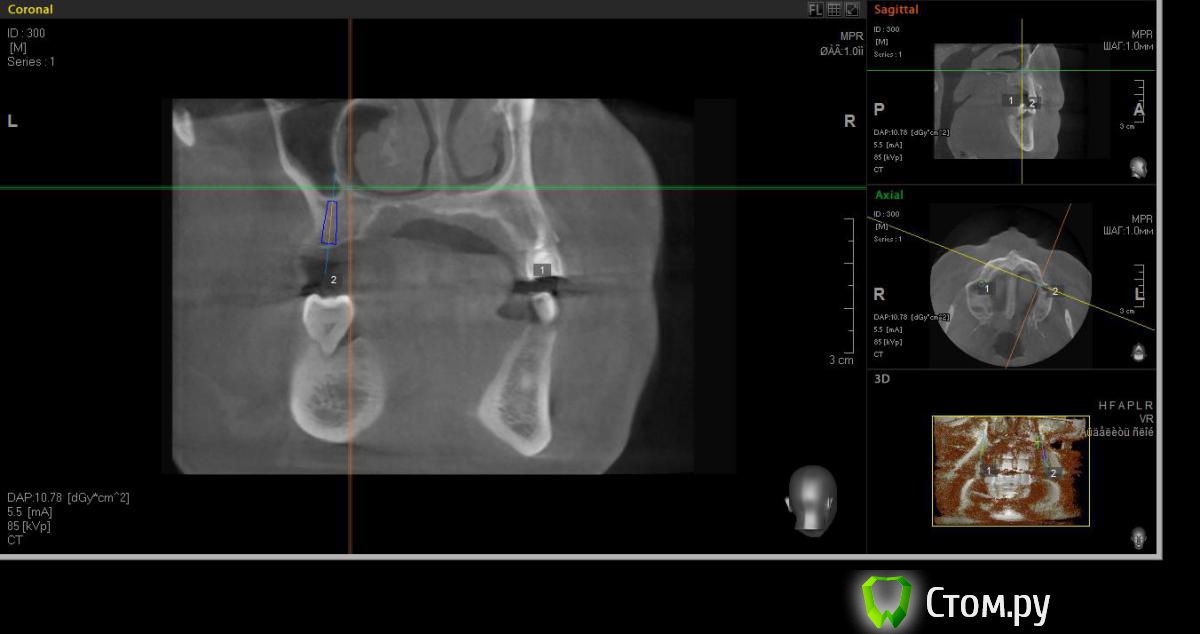

faity Опубликовано 18 мая, 2014 Автор Поделиться Опубликовано 18 мая, 2014 хочу вот так сделать, на 1.6 мягкий лифт, в обл 2.6 не лезтьвинты Ankylos 1.6- 4,5/11 2.6- 3,5/9,5кости в области 1.6- 7,5мм, должно хватить для закрытого, открытый пациент не потянет по финансам.какие мысли? Ссылка на комментарий

red_butler Опубликовано 19 мая, 2014 Поделиться Опубликовано 19 мая, 2014 Я бы не планировал хирургию исходя из финансовых пожеланий пациента, и 1.6 вел бы с открытым синусом. Представьте что при закрытом порвали мембрану, открытый придется делать, и за свой счет. Винт в позицию 1.6 поставил бы меньшего диаметра Ссылка на комментарий

red_butler Опубликовано 19 мая, 2014 Поделиться Опубликовано 19 мая, 2014 (изменено) Не знаю диаметры винтов в этой системе, между 3.5 и 4.5 Промежуточного нет?А 2.6 без синуса и диаметр больше Изменено 19 мая, 2014 пользователем red_butler Ссылка на комментарий

faity Опубликовано 19 мая, 2014 Автор Поделиться Опубликовано 19 мая, 2014 Не знаю диаметры винтов в этой системе, между 3.5 и 4.5 Промежуточного нет?А 2.6 без синуса и диаметр большепромежуточных к сожалению нета 2,6 больше не получитсяэто при ныненшнем радиусе и положении, если делать больше винт, то больше углублять, а тогда в синус провалюсь Ссылка на комментарий